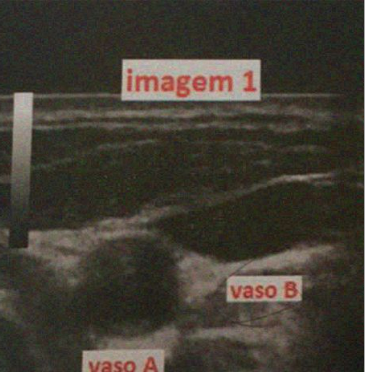

Como diferenciar uma veia de uma artéria no USG? E um trombo?

-Artérias: paredes espessas, formato arrendodado, não compressibilidade e fluxo pulsátil ao Dopler.

-Veias: paredes finas, menos arrendodadas, COMPRESSÍVEIS, Não pulsátil.

-Trombo: imagem hiperecogênica (mais branca que sangue) na luz do vaso e tbm o torna NÃO COMPRESÍVEL